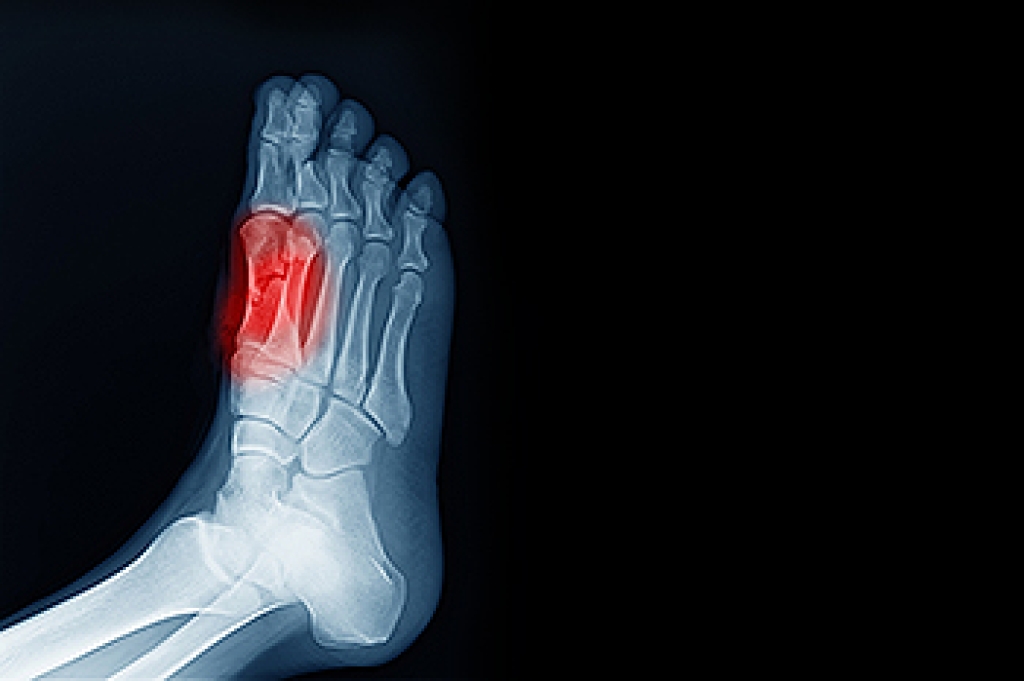

- Vertical talus, where the talus bone forms in the wrong position causing other bones in the foot to line up improperly, the front of the foot to point up, and the bottom of the foot to stiffen, with no arch, and to curve out.

- Tarsal coalition, when there is an abnormal connection of two or more bones in the foot leading to severe, rigid flatfoot.